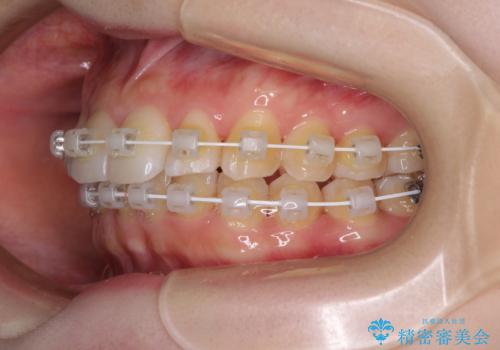

- 矯正装置

- 審美装置

半年もせずにインビザラインを全く使用することができなくなってしまったので、治療開始から1年ほどでワイヤー矯正へ変更することとなりました。

ワイヤー矯正へ変更してからはあっという間に治療が進み、1年弱で終えることができました。